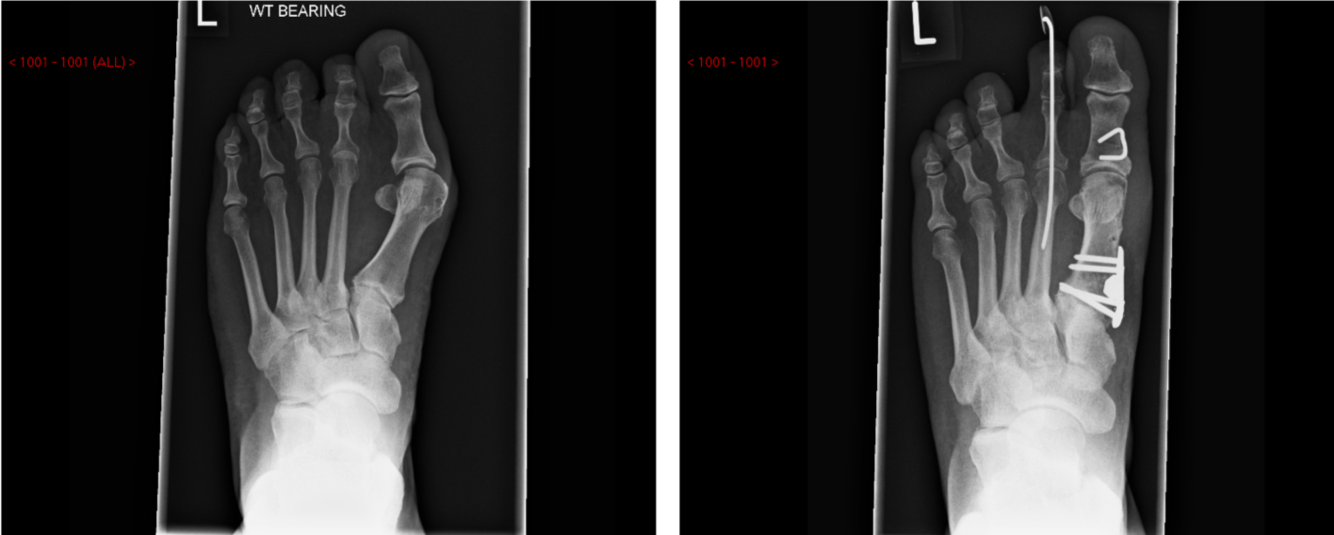

Hallux Valgus – Scarf osteotomy

Bone broken and shifted in the coronal plane

Hallux Valgus – basal osteotomy